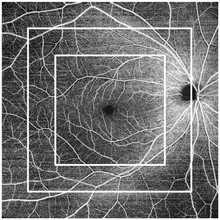

- Wide, deep, high-resolution imaging:

With RS-1 Glauvas, a single B-scan image clearly presents the area from the optic nerve head to the temporal vascular arcade, and the 4.2 mm depth B-scan imaging readily captures the oblate retinal shape of myopic eyes. Improvements in AngioScan OCT-Angiography include wider and clearer images for assessing chorioretinal microvasculature.